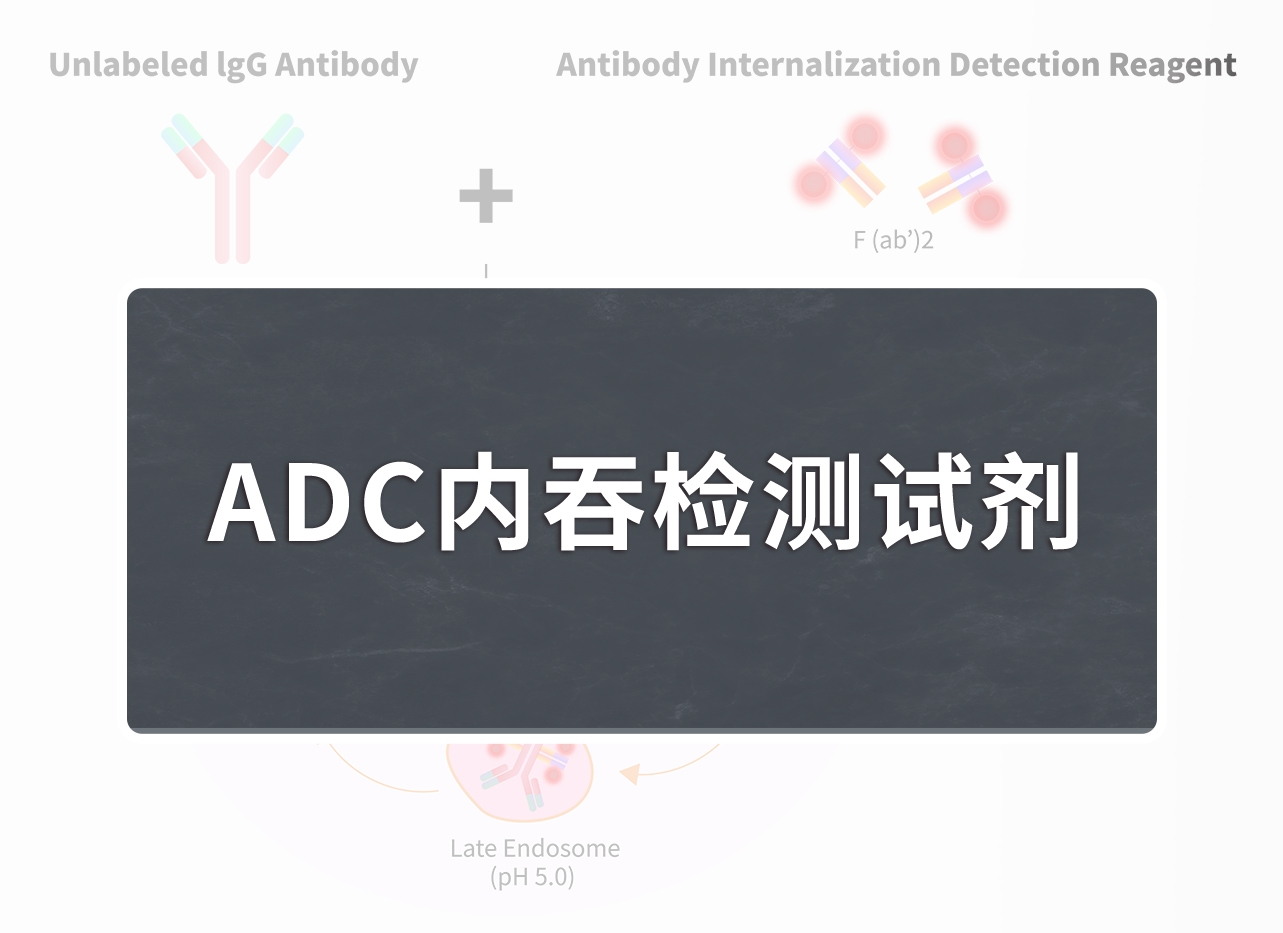

TROP2因其偶联药物“戈沙妥珠单抗”获批用于治疗三阴性乳腺癌而被越来越多的人所熟知。ADC药物开发成功的关键在于选择单克隆抗体特异性识别的靶点,TROP2在多种恶性肿瘤中均发生过表达,是单抗、ADC药物开发的首选靶点。

如表所示,TROP2靶向药物的开发主要集中在单抗、ADC方向,药物适应症为三阴性乳腺癌、尿路上皮癌、非小细胞癌及其他多种实体瘤。在临床前TROP2靶药研究中,除了靶向TROP2的单抗ADC药物外,靶向CD3-TROP2双抗、CAR-T以及CAR-NK等方向的药物研究也在进行中。